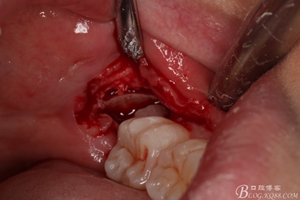

圖10. 翻開瓣。38牙冠還有部分骨質(zhì)覆蓋,遂用高速牙鉆去骨

圖11.去骨---暴露出38的牙冠最大周徑